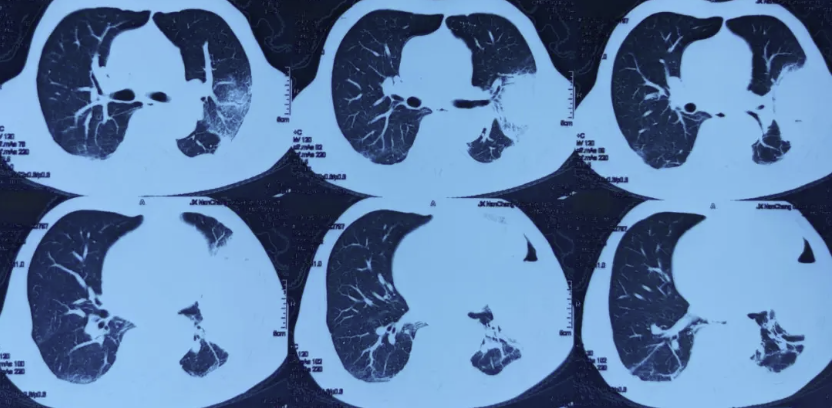

现病史:患者1个月前参加酒席后出现咳嗽、咳脓痰,伴畏寒发热,体温38度,于当地市人民医院就诊,2026年1月19日行胸部CT检查示:两肺感染可能,双肺多发小、微结节,心包、左侧胸腔少量积液(图片1)。予左氧氟沙星输液治疗,仍有发热伴咳嗽咳痰,间断有少量痰血,再次就诊于当地市人民医院,2026年1月31日行气管镜检查,灌洗液mNGS提示:惠普尔养障体 序列数283,小孢根霉 序列数66,建议患者至省会医院进一步就诊。2026年2月5日患者于当地省会医院住院,予静脉输注艾沙康唑抗真菌治疗,2026年2月9日行胸部增强CT检查示:左上胸膜下大片状高密度影伴明显坏死、积气,结合临床符合毛霉病并胸膜侵犯,双侧胸腔少量积液,左侧部分包裹性改变(图片2)。因患者病灶较前增大,病情进展,家属要求转院至上海治疗。

图片1:2026年1月19日当地市人民医院胸部CT示两肺感染可能,双肺多发小、微结节,心包、左侧胸腔少量积液。